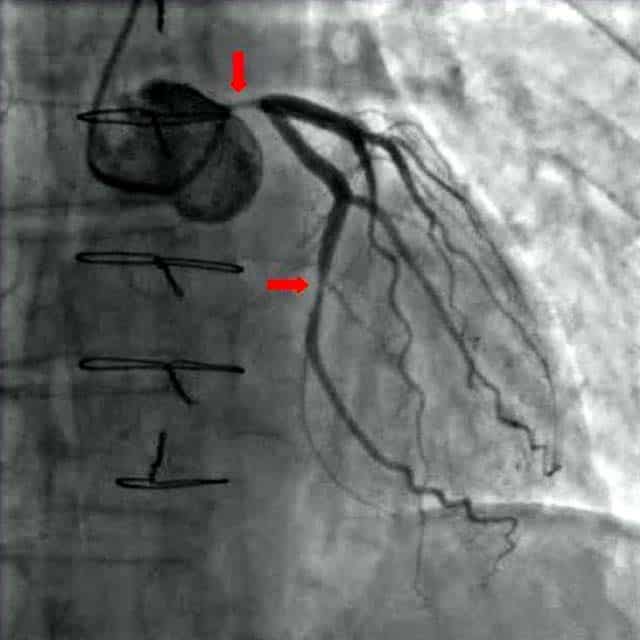

The entire body must be supplied with nutrients and oxygen via the circulatory system and the heart is no exception. The coronary circulation refers to the vessels that supply and drain the heart. Coronary arteries are named as such due to the way they encircle the heart, much like a crown. This article will outline the naming, distribution, and clinical relevance of vessels in the coronary circulation. Pro Feature - 3D Model You've Discovered a Pro Feature Access our 3D Model Library Explore, cut, dissect, annotate and manipulate our 3D models to visualise anatomy in a dynamic, interactive way. Learn More Naming Coronary Arteries There are two main coronary arteries which branch to supply the entire heart. They are named the left and right coronary arteries, and arise from the left and right aortic sinuses within the aorta. The aortic sinuses are small openings found within the aorta behind the left and right flaps of the aortic valve. When the heart is relaxed, the back-flow of blood fills these valve pockets, therefore allowing blood to enter the coronary arteries. The left coronary artery (LCA) initially branches to yield the left anterior descending (LAD), also called the anterior interventricular artery. The LCA also gives off the left marginal artery (LMA) and the left circumflex artery (Cx). In ~20-25% of individuals, the left circumflex artery contributes to the posterior interventricular artery (PIv). The right coronary artery (RCA) branches to form the right marginal artery (RMA) anteriorly. In 80-85% of individuals, it also branches into the posterior interventricular artery (PIv) posteriorly. By TeachMeSeries Ltd (2025) Fig 1Anterior view of the arterial supply to the heart. By TeachMeSeries Ltd (2025) Fig 2Overview of the branching structure of the coronary arteries. Cardiac Veins The venous drainage of the heart is mostly through the coronary sinus – a large venous structure located on the posterior aspect of the heart. The cardiac veins drain into the coronary sinus, which in turn, empties into the right atrium. There are also smaller cardiac veins which pass directly into the right atrium. The main tributaries of the coronary sinus are: Great cardiac vein (anterior interventricular vein) – the largest tributary of the coronary sinus. It originates at the apex of the heart and ascends in the anterior interventricular groove. It then curves to the left and continues onto the posterior surface of the heart. Here, it gradually enlarges to form the coronary sinus. Small cardiac vein – located on the anterior surface of the heart, in a groove between the right atrium and right ventricle. It travels within this groove onto the posterior surface of the heart, where it empties into the coronary sinus. Middle cardiac vein (posterior interventricular vein) – begins at the apex of the heart and ascends in the posterior interventricular groove to empty into the coronary sinus. Posterior cardiac vein – located on the posterior surface of the left ventricle. It lies to the left of the middle cardiac vein and empties into the coronary sinus. By TeachMeSeries Ltd (2025) Fig 3Anterior view of the venous drainage of the heart. Supplied by the great and small cardiac veins By TeachMeSeries Ltd (2025) Fig 4Posterior view of the heart, showing the venous drainage. Pro Feature - Dissection Images Anterior view of the coronary arteries. Anterior view of the coronary arteries. You've Discovered a Pro Feature Access our Dissection Image Library Enhance your understanding with high-resolution dissection images showcasing real-life anatomy. Learn More Distribution of the Coronary Arteries In general, the area of the heart which an artery passes over will be the area that it perfuses. The following describes the anatomical course of the coronary arteries. See Appendix A for a tabular overview of the arterial distribution. The RCA passes to the right of the pulmonary trunk and runs along the coronary sulcus before branching. The right marginal artery arises from the RCA and moves along the right and inferior border of the heart towards the apex. The RCA continues to the posterior surface of the heart, still running along the coronary sulcus. The posterior interventricular artery then arises from the RCA and follows the posterior interventricular groove towards the apex of the heart. The LCA passes between the left side of the pulmonary trunk and the left auricle. The LCA divides into the anterior interventricular branch and the circumflex branch. The anterior interventricular branch (LAD) follows the anterior interventricular groove towards the apex of the heart where it continues on the posterior surface to anastomose with the posterior interventricular branch. The circumflex branch follows the coronary sulcus to the left border and onto the posterior surface of the heart. This gives rise to the left marginal branch which follows the left border of the heart. By TeachMeSeries Ltd (2025) Fig 4Anterior view of territorial arterial supply to the heart. By TeachMeSeries Ltd (2025) Fig 5Posterior view of territorial arterial supply to the heart. Clinical Relevance Coronary Artery Disease Coronary artery disease or coronary heart disease (CHD) is a leading cause of death, both in the UK and worldwide. It describes a reduction in blood flow to the myocardium and has several causes and consequences. CHD can result in reduced blood flow to the heart as a result of narrowing or blockage of the coronary arteries. This may be due to atherosclerosis, thrombosis, high blood pressure, diabetes or smoking. All these factors lead to a reduced flow of blood to the heart through physical obstruction or changes in the vessel wall. Angina pectoris is one consequence of CHD. Angina pectoris describes the transient pain a person may feel on exercise as a result of lack of oxygen supplied to the heart. This pain is felt across the chest but is quickly resolved upon rest. Exercise is a trigger for angina as the coronary arteries fill during the diastolic period of the cardiac cycle. On exercising, the diastolic period is shortened meaning that there is less time for blood flow to overcome a blockage in one of the coronary vessels in order to supply the heart. If left untreated, angina can soon progress to more severe consequences, such as a myocardial infarction. The sudden occlusion of an artery results in infarction and necrosis of the myocardium. This means a section of the heart is unable to beat (which part of the heart depends on which artery has become occluded). The ECG leads on which an MI change appears can be used to locate the artery that had been occluded as shown in the table. Description ECG leads with changes Artery occluded Inferior II, III, aVF RCA Anteroapical V3 and V4 Distal LAD Anteroseptal V1 and V2 LAD Anterolateral I, aVL, V5 and V6 Circumflex artery Extensive anterior I, aVL, V2-V6 Proximal LCA True posterior Tall R in V1 RCA Diagnosis and Treatment of Coronary Artery Disease By Maria A Pantaleo et al [CC-BY-2.0] via Wikimedia Commons Fig 1.6A coronary angiogram. Two critical narrowings have been labelled. A blockage in a coronary artery can be rapidly identified by performing a coronary angiogram. The imaging modality involves the insertion of a catheter into the aorta via the femoral artery. A contrast dye is injected into the coronary arteries and x-ray based imaging is then used to visualise the coronary arteries and any blockage that may be present. Immediate treatment of a blockage can be performed by way of a coronary angioplasty, which involves the inflation of a balloon within the affected artery. The balloon pushes aside the atherosclerotic plaque and restores the blood flow to the myocardium. The artery may then be supported by the addition of an intravascular stent to maintain its volume. Appendix A – Tabular Overview of the Vasculature of the Heart Artery Region supplied Vein draining region Right coronary Right atrium SA and AV nodes Posterior part of interventricular septum (IVS) Small cardiac vein Middle cardiac vein Right marginal Right ventricle Apex Small cardiac vein Middle cardiac vein Posterior interventricular Right ventricle Left ventricle Posterior 1/3 of IVS Left posterior ventricular vein Left coronary Left atrium Left ventricle IVS AV bundles Great cardiac vein Left anterior descending Right ventricle Left ventricle Anterior 2/3 IVS Great cardiac vein Left marginal Left ventricle Left marginal vein Great cardiac vein Circumflex Left atrium Left ventricle Great cardiac vein Rate This Article